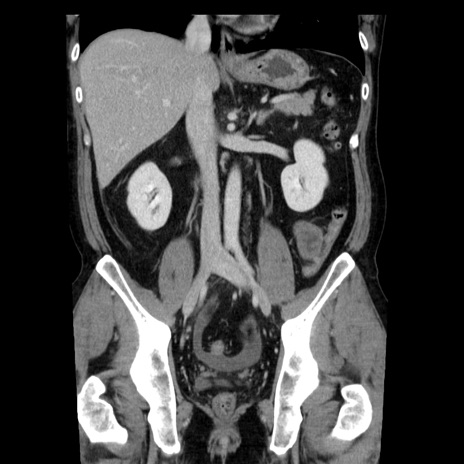

症例29(冠状断像)

【症例】40歳代男性

【現病歴】2日前から胃痛あり。徐々に周期的な激痛に変化した。本日になっても激痛があるため受診。

【身体所見】意識清明、BT 38-39℃台あり、腹部:膨満、やや硬、右下腹部に圧痛あり。

【データ】WBC 8500、CRP 23.26